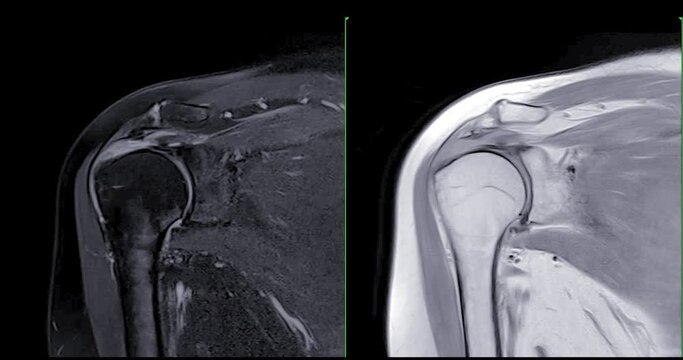

Magnetic Resonance Imaging or MRI of Shoulder Joint  Coronal T2FS and PDW  for diagnostic shoulder pain.

00:23